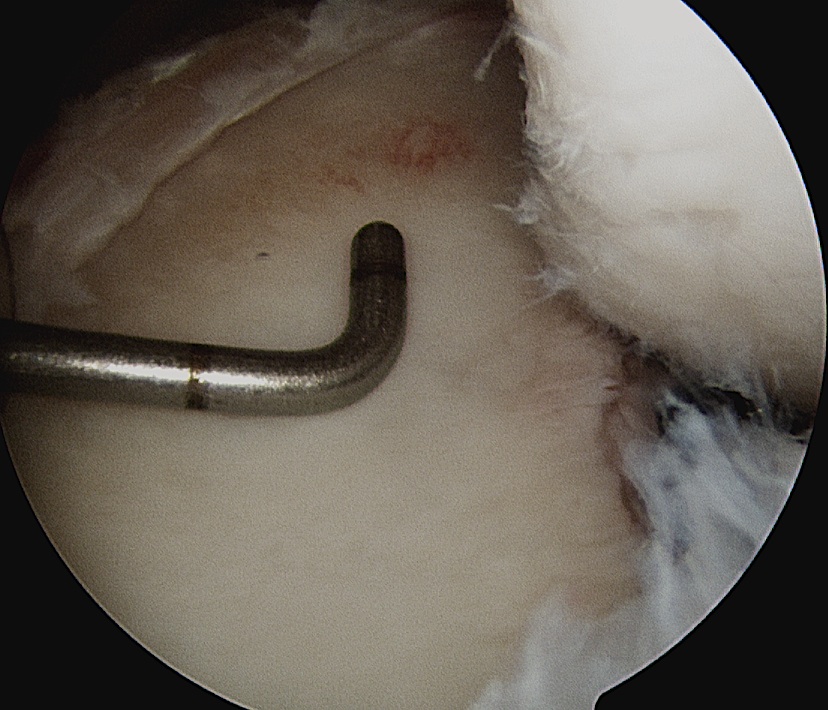

Shoulder Scope Bankart RaspShoulder Stabilisation Labral Mobilisation

Labral mobiliser / rasp

- labral tear can be obvious, but may have partially healed or healed medially

- change camera to anterosuperior portal for better view

- mobilize until can see subscapularis muscle underneath

- need to be able to advance labrum medially and superiorly for repair

Shoulder Arthoscopy Bankart MobilisationShoulder Scope Bankart Mobilisation

Shoulder Stabilisation Anterior Labral MobilisationShoulder Stabilisation Anterior Labral Mobilisation 2